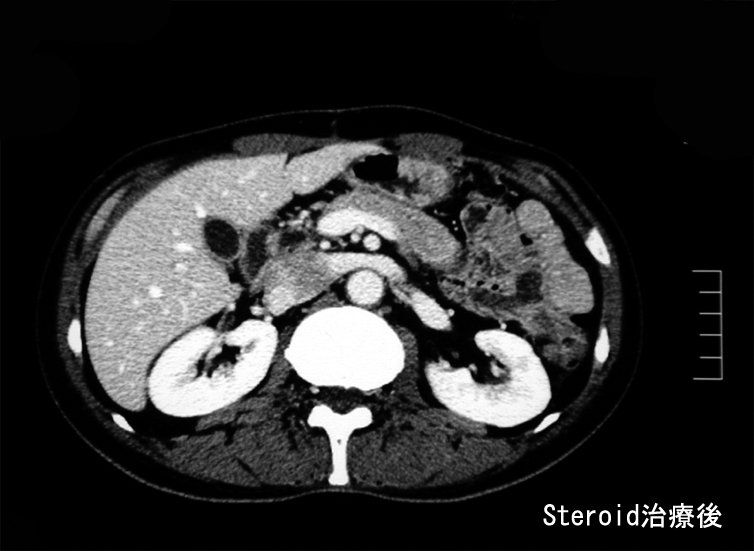

悪性リンパ腫や膵癌など悪性腫瘍は否定され自己免疫性膵炎と診断し, steroid治療を開始する。約2ヶ月の投与で, 膵、腹腔腫瘤は著明に縮小または消失しました。steroid減量中に黄疸が出現, 画像診断で硬化性胆管炎の合併をうたがいsteroidを増量、黄疸は消失。以後steroid をゆるやかに漸減し中止したが症状の再発はない。

Steroid 治療2ヶ月後のCT; 腫瘤性病変の著明な縮小と消失が確認できる。